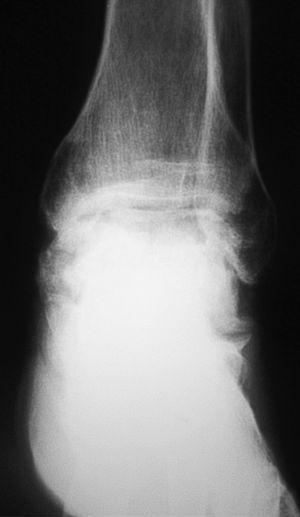

El seguimiento a la largo plazo de las fracturas del astrágalo identifica que la causa más común de los resultados pobres está asociada con la OA subastragalina, tibioastragalina y talonavicular, tanto en nuestra revisión, que alcanzó al 21% (8) de los casos (figs. 9 y 10), como en otros trabajos revisados15,17,19,22,23.

Fig. 9. --A) Fractura del cuerpo del astrágalo tipo B más rotura completa de los 3 ligamentos laterales del tobillo. B) Abordaje bilateral. Osteosíntesis. Sutura de ligamentos. Radiografía y tomografía computarizada a los 18 meses. Artrosis subastragalina y tibioastragalina.

Fig. 9. --a: Type B fracture of the astragalus with complete rupture of the 3 lateral ankle ligaments. b: Bilateral approach. Osteosynthesis. Ligament suture. Radiography and CT at 18 months. Sub-astragalar and tibio-astragalar arthrosis.

Fig.10. --Resultado a los 32 meses. 50° de BA. NAV del cuerpo y artrosis subastragalina y tibioastragalina

Fig.10. --Results at 32 months. BA 50º. Avascular necrosis of the astragalus and sub-astragalar and tibio-astragalar arthrosis.